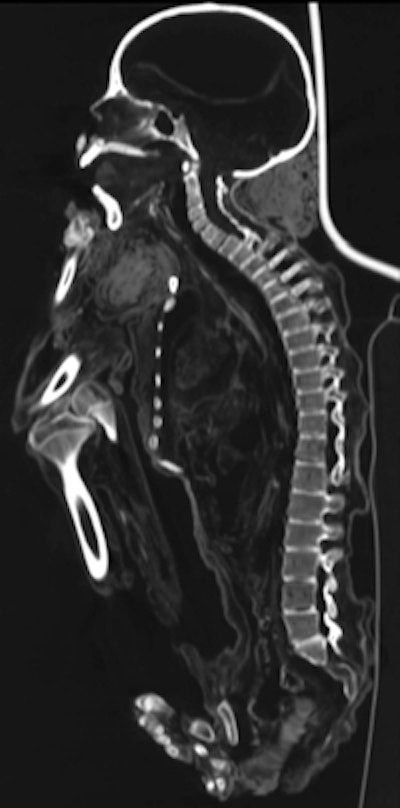

"First, the axial scans were evaluated, using different ranges of window width and window level parameters to identify structures with different densities," the authors wrote. Next, to virtually remove the bandages, "preset reconstruction algorithms for soft tissues with varying window width parameters were used to obtain the progressive elimination of external layers with a density lower than that of dried skin, starting from the bandages."

Dental conditions were compromised in seven of the mummies, including missing teeth, multiple carious lesions, and severe occlusal surface wear. The authors noted that damage was most likely due to a lack of oral hygiene, "but, especially chronic apical peridontitis, might in part also be explained by the excessive use of the coca plant (Erythroxylum coca) in the Chachapoyan culture, as in many other Andean populations, for religious and ritual purposes."

Among other findings, conditions identified in the bones included an occipital osteoma, as well as osteoarthritis or mild tuberculosis-related changes of a sacroiliac joint. A severe spondylodiscitis, a lytic lesion in the sacral bone, and erosions at one tarsal joint were also observed, which most likely represent severe manifestations of skeletal tuberculosis, the researchers noted.

Indications of pulmonary tuberculosis were also found. "Five of eight mummies showed several small intrapulmonary or mediastinal calcifications, such as those seen typically in pulmonary tuberculosis," the authors wrote.